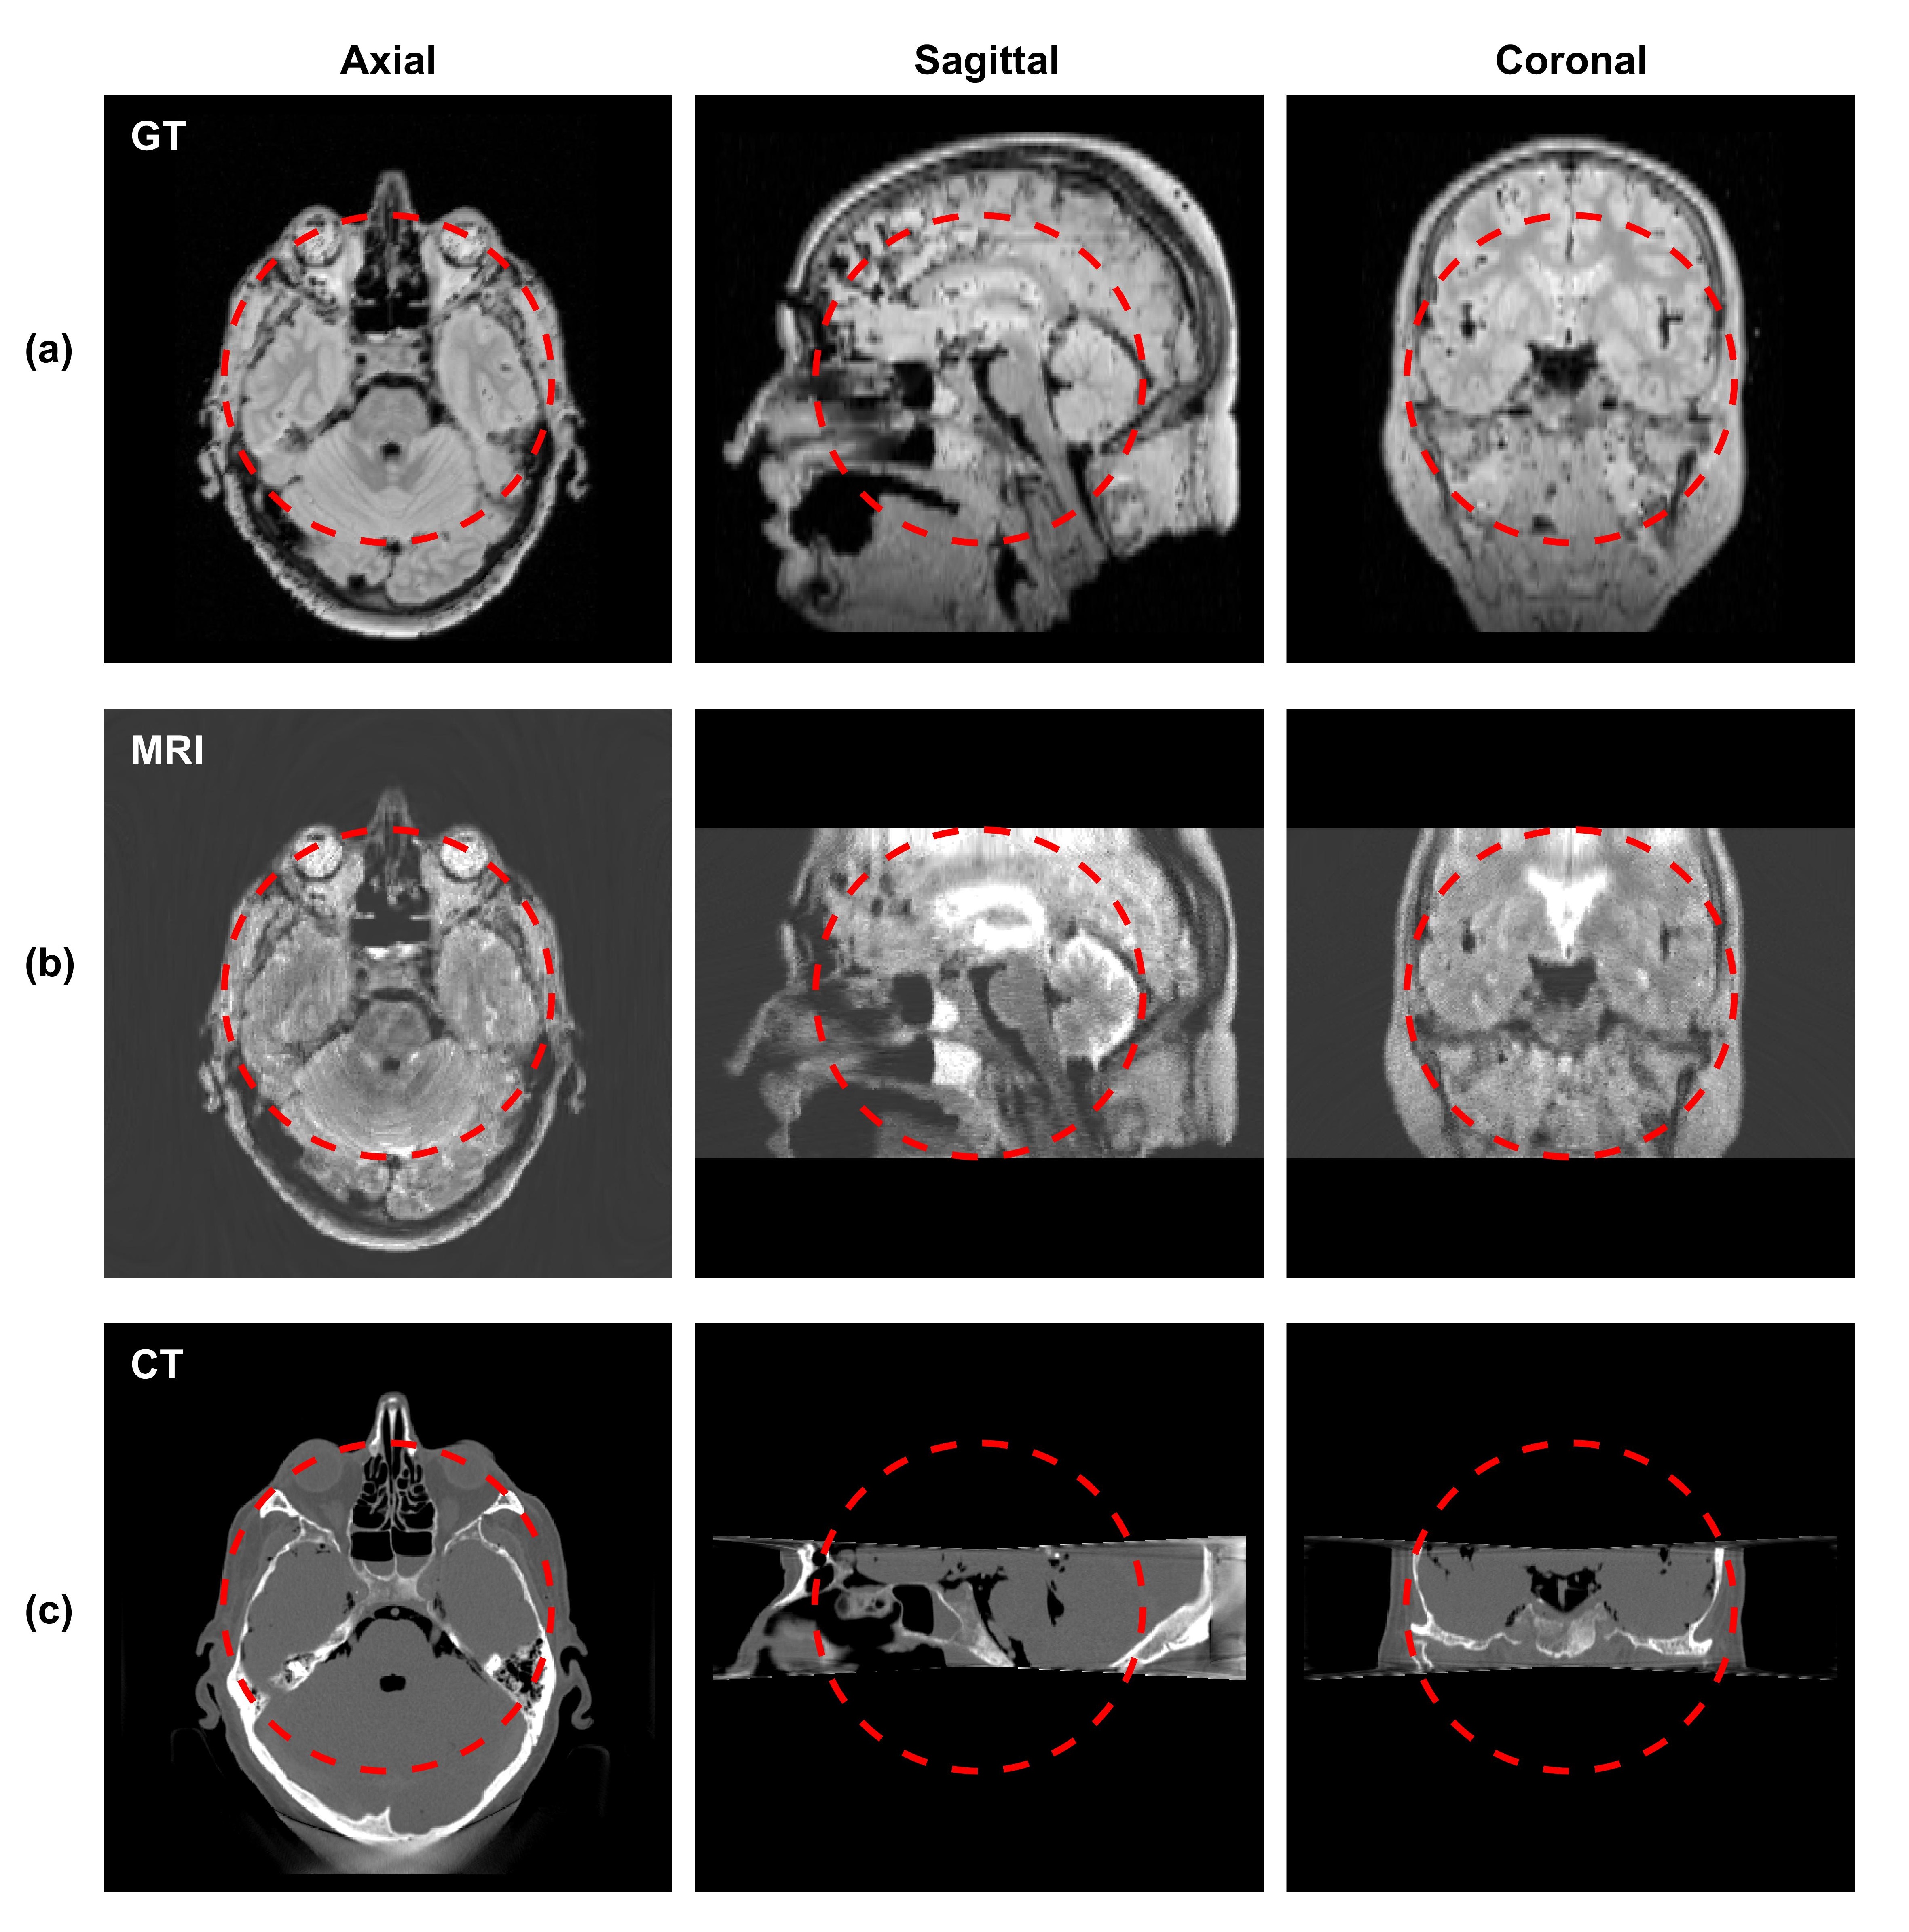

Figure 3: Orthogonal views of (a) the proton density of the 3D Shepp-logan phantom, (b) simulated MR images (TR=1,000 ms,TE=80 ms, and NEX=16), and (c) simulated CT images. The dashed red circles indicate the targeted MR FOV of 15 cm in diameter.

We first present simulation results for the Shepp-Logan phantom in Figure 3. For the MR simulation, the relaxation time TR and TE are 1,000 ms and 80 ms, respectively. The slice thickness is chosen as 4mm, and the voxel size on the axial planes is 1×1111\times 1 mm2. To reduce noise, we repeated data acquisition with the number of excitations (NEX) being set to 16. The images in Figure 3(a) display proton density of the phantom in three orthogonal views to show the structure of the phantom. Figure 3(b) shows the resulting MR image. The CT simulation results of the Shepp-Logan phantom are in Figure 3(c). The image voxel size is 0.50.50.5 mm3. Due to the narrow x-ray beam through the gap between the two magnet rings, the longitudinal coverage of the CT scan is 5similar-toabsent5\sim 5 cm.

To illustrate the performance of the proposed system with more clinical relevance, we present in Figure 6-8 results for different body sites using the VHP data. In the brain case shown in Figure 6, we remark that the relatively low resolution along superior-inferior direction in the MR image is intrinsically caused by the phantom itself. In fact, in the VHP MR image dataset the slides spacing is 3 mm, which limited the image resolution in the simulation results.

Figure 6: Orthogonal views of (a) the spin density of the VHP brain phantom, (b) simulated MR images (TR=1,000 ms,TE=80 ms, and NEX=16), and (c) simulated CT images. The dashed red circles indicate the MR FOV of 15 cm in diameter.